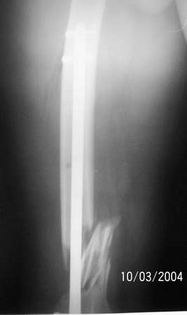

A 34 year old male was injured in a car accident.

The femur injury was treated by long retrograde interlocking nail.

I would expect healing though alignment could have been better if Poller screw or temporary wire was used.

It was used ORTHFIX Retrograde nailing System, diameter 11.